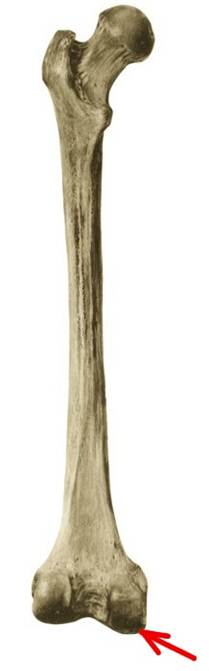

S: Стрелка указывает на trochanter minor

S: Стрелка указывает на linea supracondylaris medialis

S: Стрелка указывает на linea supracondylaris lateralis

S: Стрелка указывает на linea supracondylaris medialis

S: Стрелка указывает на condylus medialis

S: Стрелка указывает на crista intertrochanterica

S: Стрелка указывает на linea aspera

S: Стрелка указывает на facies poplitea (латинский язык).